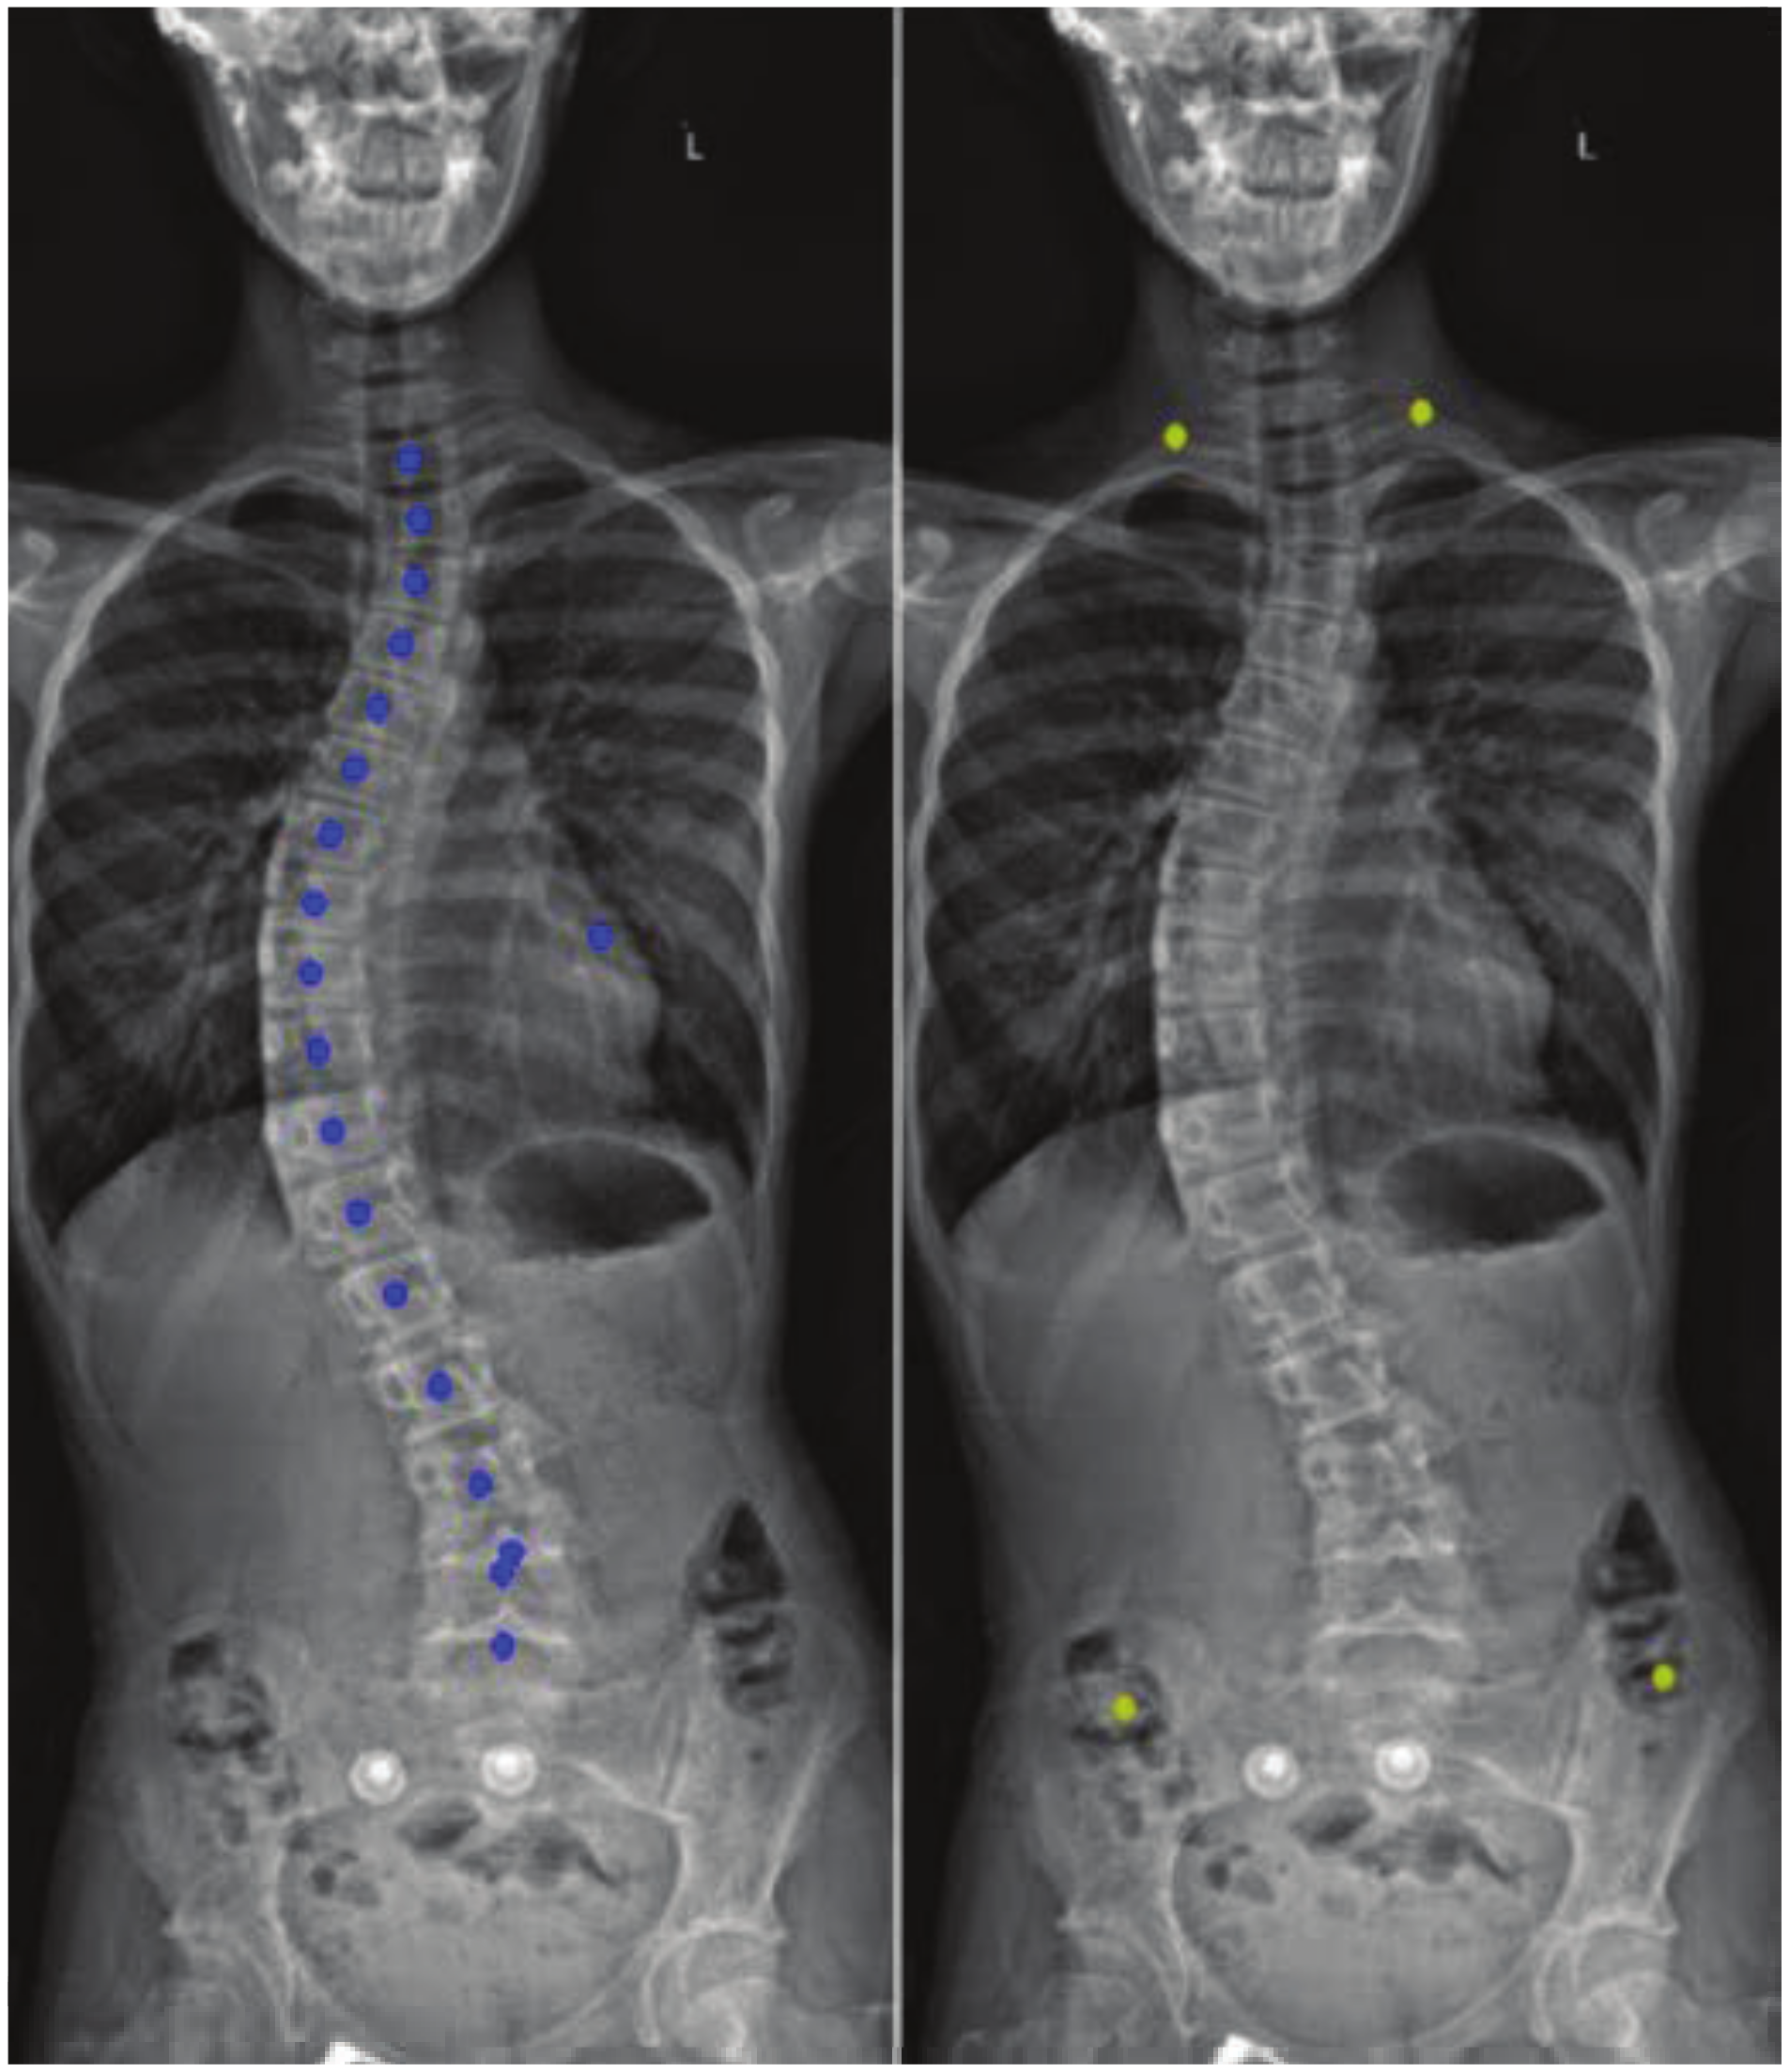

4. Results